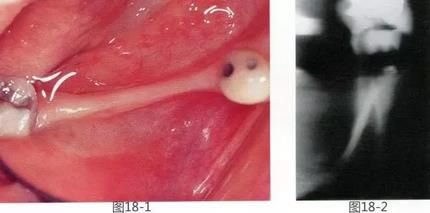

360截圖20170422142229805.jpg

圖19-11   FGG后4個(gè)月的狀態(tài)。牙體周圍獲得了充分寬度的附著齦。

圖19-12  同時(shí)期的咬合面照。與圖19-2相比寬度和高度都得到了很好的恢復(fù),提高了橋體部的美觀性,清潔性。